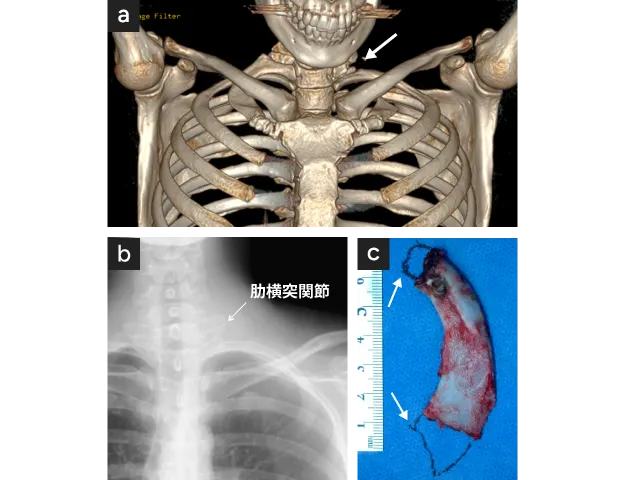

外科治療では、鎖骨上と鎖骨下の2か所に切開を加えます。鎖骨下動脈病変は頚肋に起因する例が多く、頚肋を認める場合には、まずこれを切除します〈図18a,b,c〉。さらに通常、第一肋骨切除および前・中斜角筋切離を行います。

図18

図18. 頚肋を伴う左動脈性胸郭出口症候群

• 左頚肋typeIII XP(矢印)

• 左頚肋typeIII CT(矢印)

• 鎖骨上切開創からみた第一肋骨(矢印)とそれに付着するtypeIIIの頚肋(太矢印)